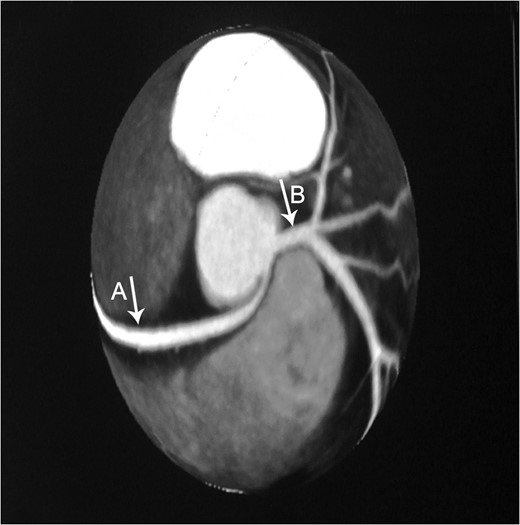

Axial CTA demonstrates an anomalous origin of RCA (Arrow A) which arises as a branch from LMCA (Arrow B).

Constructional CT demonstrates an anomalous origin of RCA (Arrow A) which arises as a branch from LMCA (Arrow B).

This previously asymptomatic 37-year-old patient presented with continuous complaints of dyspnea on exertion associated with chest pain. Making her candidate for CTA which demonstrated the very rare anomalous origin of the RCA as a proximal branch from the LMCA that then continues between the pulmonary artery and ascending aorta where it is slightly compressed during systole. This finding provides us with the explanation of the presenting symptoms of such a case, which is supported by Grollman et al. ateriographic study [5].